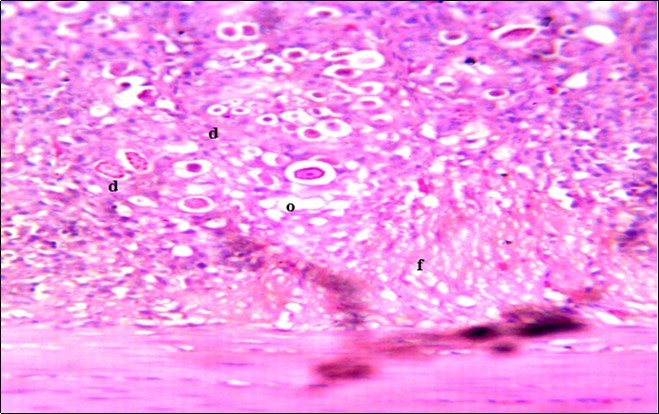

In this study, the reduction in oocyst count observed in the treated group was compared with amprolium could be attributed to the presence of a bioactive compounds azadiractin A which is known to bind membrane cholesterol, altering the integrity of the parasite membrane, resulting in loss of homeostasis and eventual death of the parasite 29]. Also, limonoids contained in NeemAzal® inhibit protein digestion and uptake of vitamins and minerals by the parasites in the gut 17. This action results in impaired nutrient utilization, reduced growth, and multiplication of the parasite which could contribute to the reduced oocyst count observed. Extracts of neem and mahogany when used individually have been reported to reduce oocyst count in avian coccidiosis 11,12. The observed reduction in oocyst count and the significant increase in weight gain of the birds when treated with NeemAzal®, as compared with the negative control group could probably be due to the inhibition of inflammation in the intestinal mucosa which is suggestive of an increased nutrient absorption across the intestinal wall and enhanced feed conversion ratio compared to the negative control this is in agreement with reports by Nwosu et al.12 and Biu et al.11 who also reported an increased weight gain and feed conversion ratio in birds treated with only Khaya senegalensis extracts and Azardiractaindica, respectively. The observed increase in RBC and haemoglobin concentration is indicative of the erythropoieticability of the NeemAzal®, which is beneficial since the Eimeria parasite in the epithelia of the intestines causes bloody diarrhoea and consequently anaemia (Table 1). This finding is in consonance with 15 who reported an anti-anaemic effect of Khaya Senegalensis on phenyl hydrazine-induced anaemia in rats. Neem has been shown to possess anti-anaemic properties in rats 14. The significant increase in mean weight gain in treated birds when compared to the negative control is possibly due to the inhibition of inflammation in the intestinal mucosa which is suggestive of an increased nutrient absorption across the intestinal wall and enhanced feed conversion ratio compared to the negative control. Nwosu et al.12 and Biu et al.11 reported an increased weight gain and feed conversion ratio in birds treated with only Khaya Senegalensis andAzadiractaindica extracts, respectively. In a similar study, Neem acts like toltrazuril exhibiting anticoccidial. In addition, exposure of broiler chickens to 20000 Oocysts of Eimeria tenellacaused generalized degeneration of the caecal glands with massive Oocysts and gametocyts within the caecal glands with fibrosis (Figure 3, Figure 4 & Figure 5), however, broiler chickens treated with NeemAzal® post exposure to 20000 Oocysts of Eimeria tenella, shows equal numbers of caecal tissues with non-observable histopathological lesions (Figure 4), possibly due to the antioxidant and anti-coccidian effects of NeemAzal®. The exact mechanism of action of neem against coccidian parasites is unknown, but a report by the National Research Council 1992 30, suggested that aqueous neem leaf extract, when taken orally, produces an increase in red cells, white blood cells and lymphocyte counts thus enhancing the cellular immune response, increasing antibody production and so most pathogens can be removed before they cause the symptoms associated with disease this was in agreement with this study as seen in Table a remarkable increase of the RBCs.

Figure 5.Photomicrograph of caecum of chick administered 20000 Oocysts of Eimeria tenella and treated with NeemAzal® Oil showing generalized degeneration of the caecal glands (d), moderate Ocysts presence (o) with fibrosis (f) X250 (H & E).

In addition, the generalized degeneration of the caecal glands, moderate numbers of gametocytes within the glandular regions with fibrosis which underscores reparative process in response to injury evoked by coccidiosis in the chicks which was perhaps brought about by the antioxidant and chemotherapeutic effect of NeemAzal®. The observed increase in RBC and hemoglobin concentration (Table 1) is indicative of the erythropoieticability of NeemAzal®, which is beneficial since the Eimeria parasite in the epithelia of the intestines causes bloody diarrhea and consequently anaemia. This finding is in consonance with 15 who reported an anti-anaemic effect of Khaya senegalensis on phenyl hydrazine-induced anaemia in rats. If the results of this study are juxtaposed with the results of the previous studies on potent antioxidant, hepatoprotective and mitigative role of methanolic extracts of Azadirachtaindica,in both natural and experimental infection with Eimeria species and can be deduced that, NeemAzal® could be said to be a potent antioxidant, chemotherapeutic and tissue protective agent. This study also answered a question on further study advocated to determine the maximum safe levels of neem supplementation because the higher doses, due to its bitterness, may show adverse effects on feed intake which will change the performance parameters of birds (Figure 6 and Figure 7) . Light microscopic inspection of hematoxylin and eosin-stained sections revealed that the epithelial cells of the Cecum were infected by E. tenella(Figure 3 and Figure 4). The results of the safety study showed that exposure of chickens to NeemAzal® at 200mg/kg body weight did not alter the histoarchitecture of liver and kidney (Figure 6 & Figure 7) which is similar to the work conducted in the same environment by a group of Scientists 34. It is therefore recommended that NeemAzal® could be used as a coccidiostat to replace the expensive anti-coccidiostats in the market.